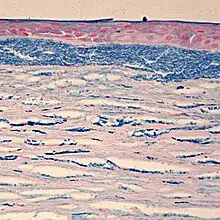

| Colloidal iron staining shows deposition of glycosaminoglycans in the cornea | |

Macular Corneal Dystrophy is an autosomal recessive genetic disorder caused by mutations in the carbohydrate sulfotransferase gene (CHST6), resulting in abnormal proteoglycan synthesis. The accumulation of abnormal glycosaminogycans in the corneal epithelium and stroma leads to progressive opacification of the cornea and subsequent loss of visual acuity.[7][8] There are three variants of MCD characterized by immunophenotype:

Histopathological staining shows characteristic alcian blue-positive deposits.[7] Various imaging modalities, including confocal microscopy and ocular coherence tomography, can provide information about the changes within the cornea and may be suitable replacements for tissue biopsy and excision.[8]